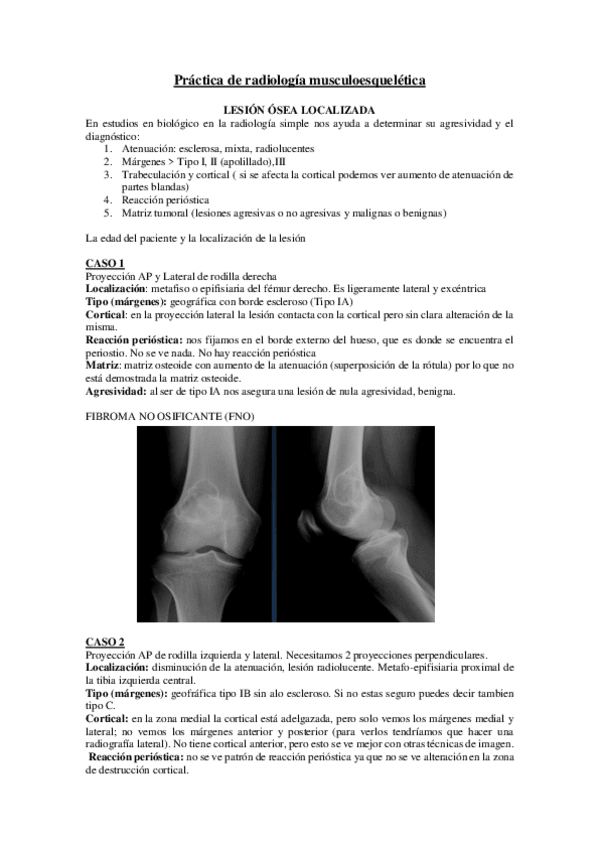

He publicado nuevos practicas de 2º Radiologia General: Practicas-Radiologia.-MSK.pdf

Practica-musculoesqueletico.pdf

Practicas-Aparato-Locomotor.pdf

PRACTICA-LOCOMOTOR.pdf